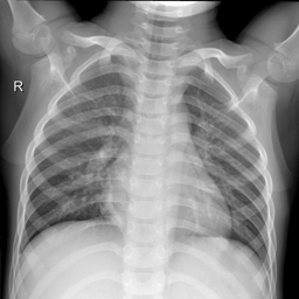

To test how good our proposed method is, we used chest X-rays of COVID19 patients, healthy patients, patients with opaque lungs, and patients with viral pneumonia. We collected images from two publicly available data sets.

COVID19 X-ray database dataset [14] [19]. This was created by a team of researchers from various universities, in cooperation with doctors from Malaysia. They examined various X-rays and classified them into COVID-19, Viral Pneumonia, Lung Opacity and Healthy chest X-rays.

COVID-19 image from the COVID19 X-ray database[14] [19] was originally around 3500. We upsampled it to 7,000 by using various image augmentation techniques. We then took equal samples of images from Viral Pneumonia, Lung Opacity and Healthy chest X-rays for the Non-COVID class.

III-B Dataset Preprocessing

The COVID-19 images are up-sampled using image augmentation techniques with the help of albumentations [13] library. The chest X-ray is flipped vertically or horizontally, then randomly rotated to the limit of 270 degrees with constant edges, and the brightness and contrast are arbitrarily adjusted to the limit of 0.4.

chest X-rays are of different sizes from 447 × 530 to 4200 × 3290 pixels. Therefore, we made the target size of images as 224 x 244 pixels. As the models were pretrained on RGB images, we created fake RGB images by stacking the channel over itself. Contrast Limited Adaptive Histogram Equalization (CLAHE) [13] is used as an image enhancement method. CLAHE is a revision of Adaptive Histogram Equalization (AHE) that avoids excessive contrast enhancement in the image.

The COVID-19 viral infection is a global pandemic and is rapidly mutating. The lungs of the infected people are inflamed due to this viral infection. Hence, examining chest X-rays is one of the possible approaches in the detection of COVID-19. In this study, we have proposed an automated and accurate technique for distinguishing COVID-19 cases from Viral Pneumonia, Lung Opacity, and Healthy chest X-rays. We experimented with four different transfer learning-based architectures and, their performance is evaluated based on four performance metrics. The results of ViT-B/32[18] confirm that transformer-based models are on par with professional radiologists.